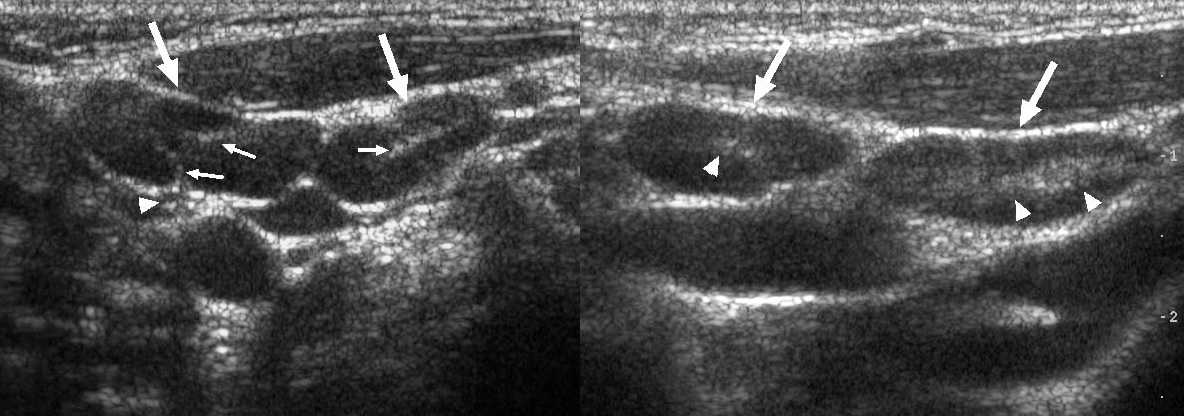

Рисунок. У детей с ОРВИ на УЗИ увеличенные шейные лимфоузлы с сохранной архитектурой — овальной формы, контур четкий и ровный, гипоэхогенные по периферии с гиперэхогенным центром. Заключение: Лимфаденопатия шейных лимфоузлов.

Рисунок. Мальчик 6-ти месяцев с выраженным дерматитом. На УЗИ шейные (1) и подчелюстные (2) лимфоузлы увеличены, вытянутой формы, гипоэхогенные по периферии с гиперэхогенной линейной структурой в центре

Обратите внимание подчелюстной лимфоузел с волнистым контуром. Заключение: Лимфаденопатия шейных и подчелюстных лимфоузлов